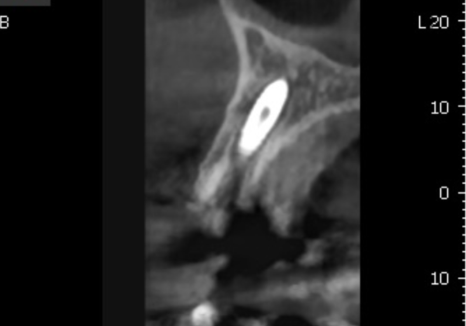

231124

수술 부위의 염증을

최대한 깔끔하게 긁어내고,

그 자리에 바로 뼈이식과 임플란트를 심어드려

외과적 수술을 단 한 번으로 끝내 드렸습니다.